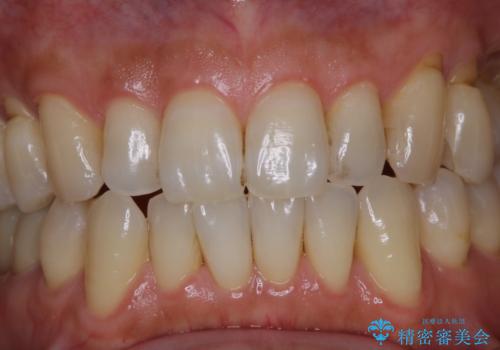

- PMTCでのメンテナンスを定期的に行っている方です。PMTC30分コースを行いました。

日々の磨き残しなどをそのまま放置すると、細菌が固まり硬い歯石になります。

歯石になってしまうと、とても硬く、歯ブラシで取り除くことが出来なくなります。

よって、歯科衛生士による専門的なクリーニングを定期的に行うことがとても大切です。

メンテナンスの間隔は個人差がありますが、基本的には2~3カ月に一度行うことをおすすめしています。